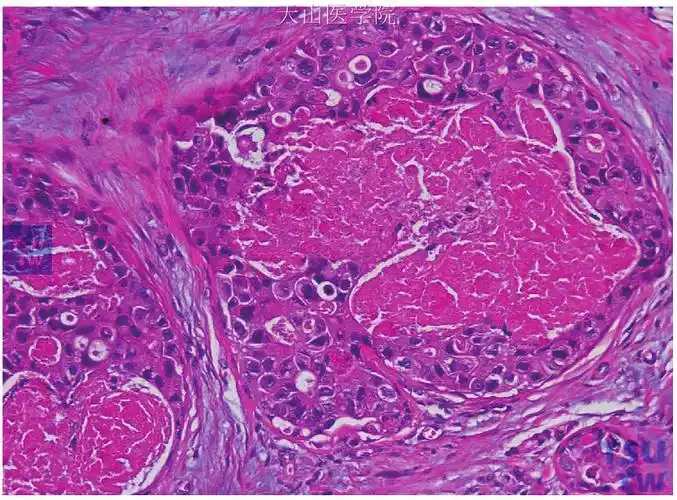

乳腺导管原位癌病理图片

乳腺导管原位癌伴局灶微小浸润一例